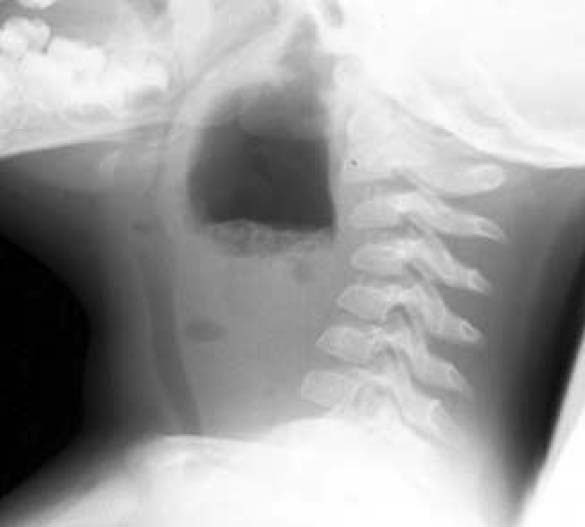

Medicine Hack Retropharyngeal abscess Xray